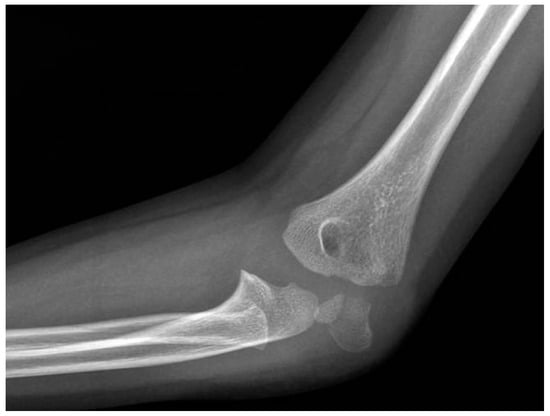

Lateral Humeral Condyle Fracture in Childhood: Results of a New Surgical Technique